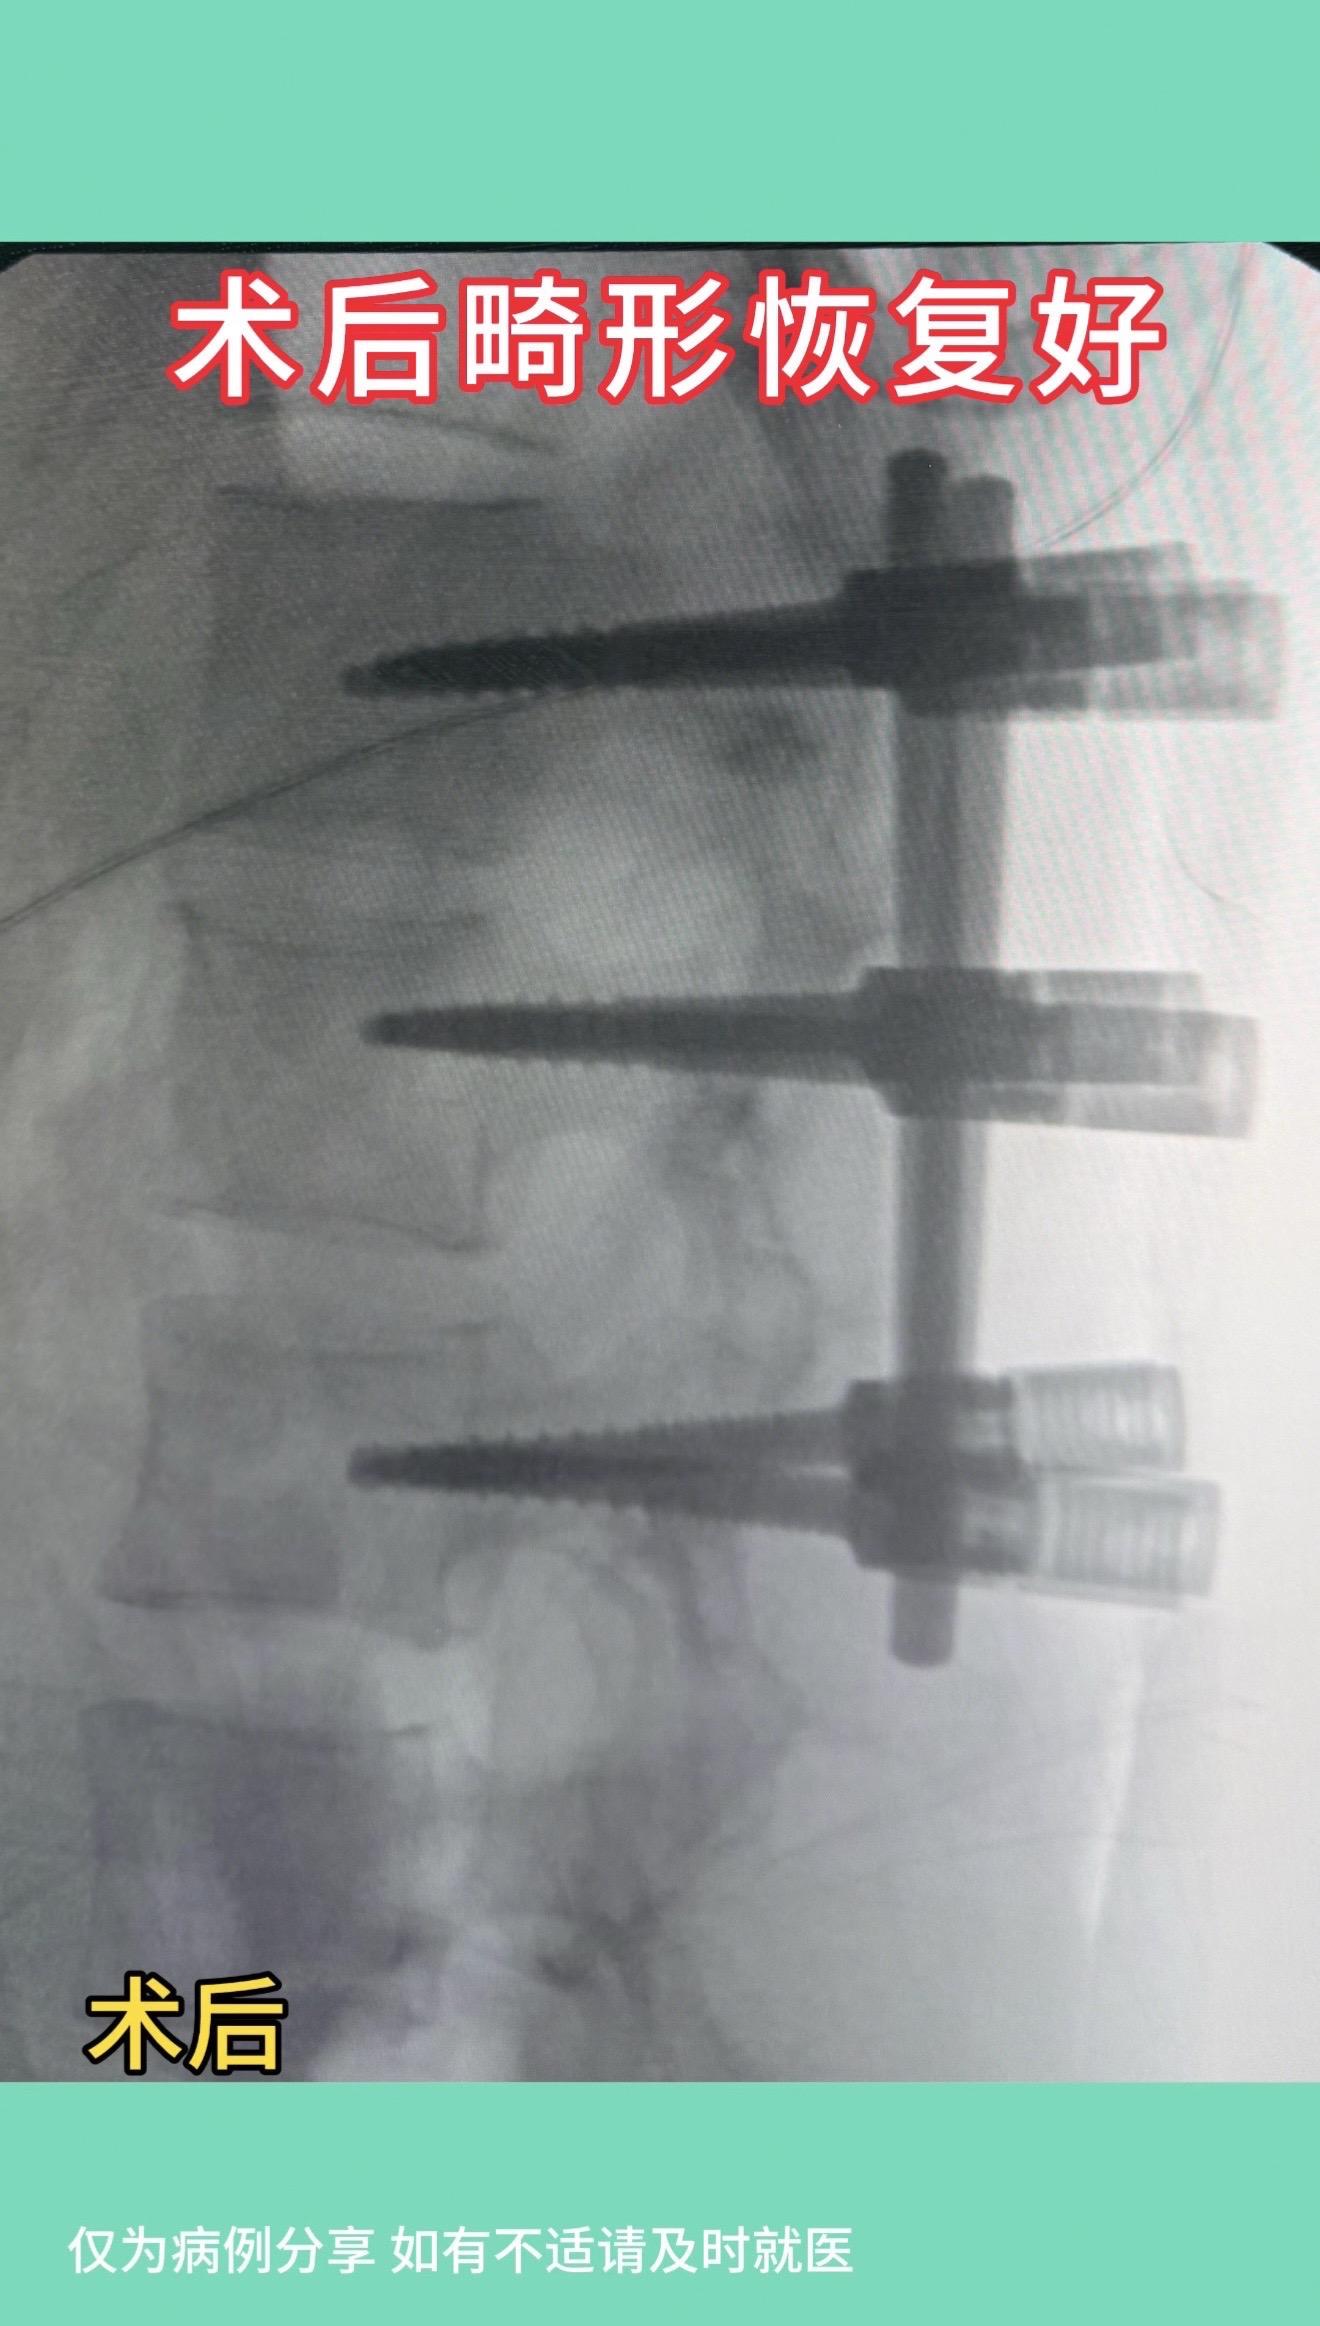

17岁女孩,车祸后腰1骨折伴侧弯,旋转畸形。术后畸形恢复好。